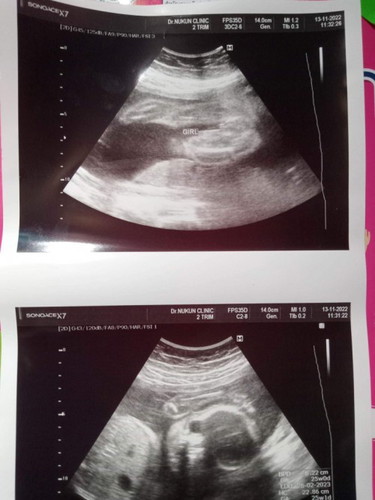

ขอดูภาพอัตต้าซาวเพศหญิงหน่อยค่ะ

ขอดูภาพอัตต้าซาวเเม่ๆหน่อยค่ะ หมอบอกว่าได้ลูกสาว อยากรู้ว่าชัวส์ไหมค่ะ

ของเค้าได้มาแบบนี้ค่ะ ลูกสาว

ตรงเม้าส์ชี้เลยค่ะ

ลูกสาวค่ะ